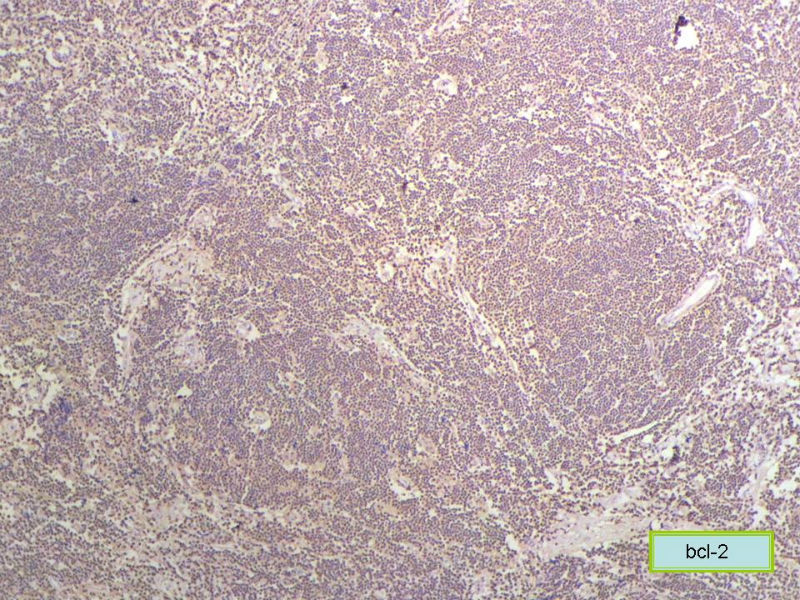

请再标记CD20和CD79a!图片中阳性不明确,根据T细胞标记看,应该是B细胞结节。Ki67散而少,不支持低级别滤泡性淋巴瘤,若B细胞弥漫阳性,则是惰性B细胞非霍奇金淋巴瘤,首先考虑套细胞,然后是边缘区淋巴瘤。不做生发中心标记,Bcl-2在小B细胞淋巴瘤分类中无意义。

CD20(+),Kappa(+),ki-67(+)>2%,Lambda(+),Pax-5(+),符合粘膜相关淋巴瘤。

赞成以上专家的讨论,根绝病史,HE形态考虑小细胞病变,CD3、CD5散在+,还是倾向淋巴造血系统病变,CD20、CD79a阳性不明确,可以考虑复查,加做PAX-5,核阳性容易判断,另再加做鉴别其它小细胞肿瘤的抗体:CD99、CD43、CyclinD1、CK、CgA、Syn等,了解病史:骨髓、末梢血、肝、脾等。